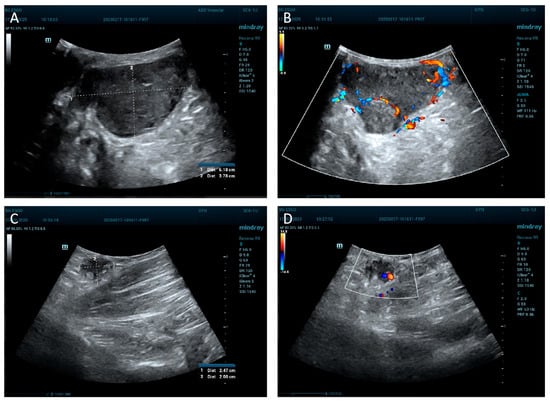

2. Case Report